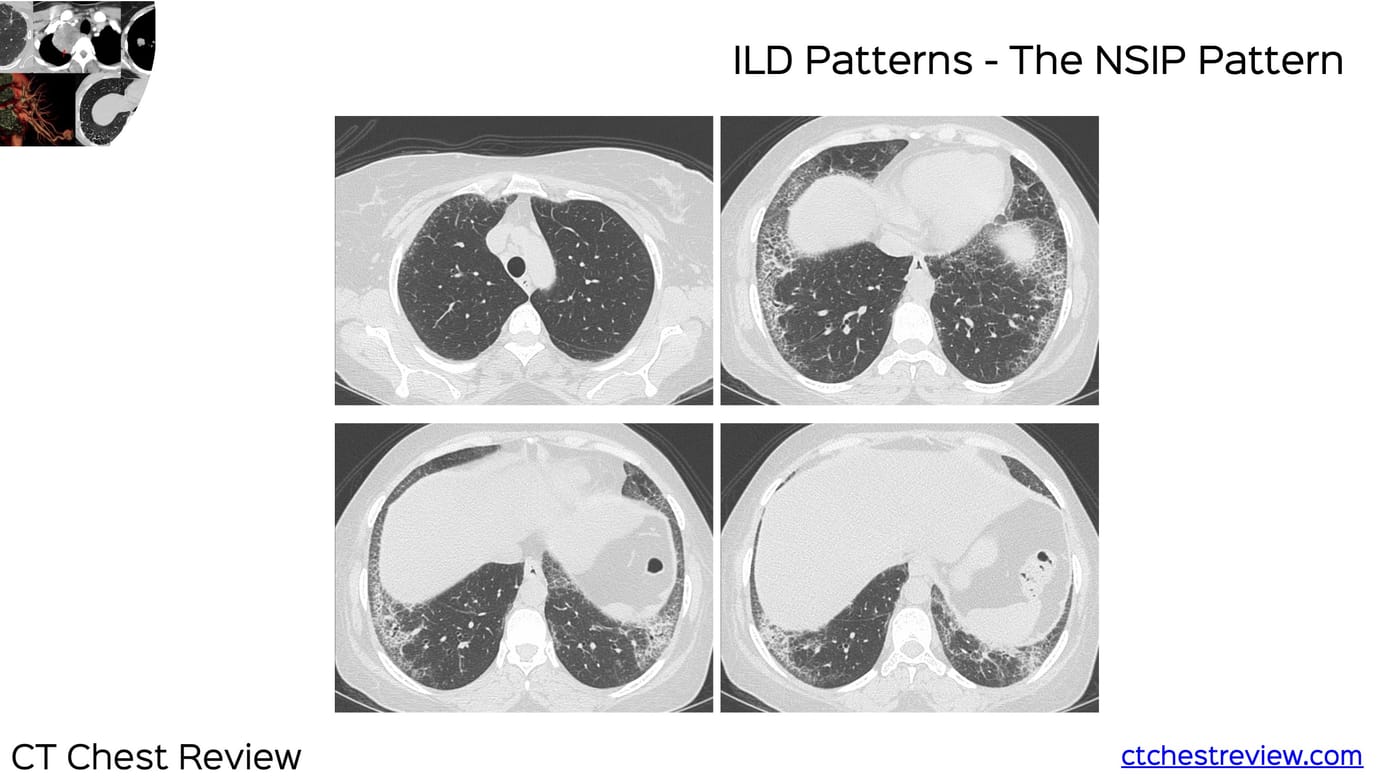

ILD Patterns - The NSIP Pattern

NSIP presents typically with spatial and temporal homogeneity and may have cellular/inflammatory and fibrotic components. There may be subpleural sparing. It is almost always a result of an underlying etiology like connective tissue disease (CTD).